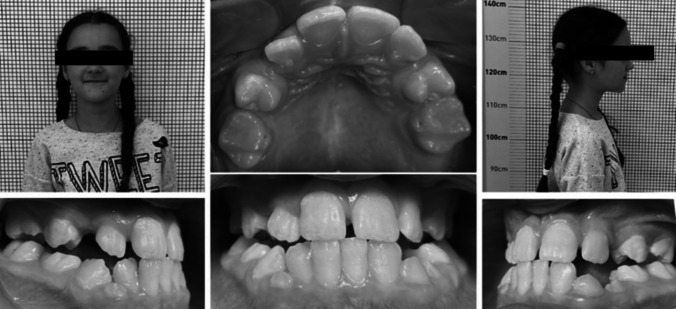

恒前牙的延迟出牙,伴随着牙弓空间不足,是混合牙列的重要挑战。本研究的目的是评估一种改良的正畸矫治器的有效性,该矫治器结合了上颌横向扩张和上颌中远端延伸,并控制恒磨牙的远端,用于治疗混合牙列期间前牙延迟萌出的病例。本研究包括前瞻性比较设计,研究组35例患者和对照组32例患者,均表现出恒前牙延迟萌出的临床和放射学征象。研究组接受改良的正畸矫治器的治疗,旨在同时实现上颌扩张和磨牙远端。对照组采用Haas矫治器进行上颌扩张,远端喷射器进行磨牙远端拔除。使用统计检验确定显著性水平,计算关键结果的p值。研究显示,改良的正畸矫治器与对照组相比,显著减少了在牙弓内创造足够空间所需的治疗时间(p = 0.017)。研究组并发症发生率为17.14%,低于对照组28.12%,差异有统计学意义(p = 0.046)。研究组患者的积极感知率(68.57%)高于对照组(43.75%),差异有统计学意义(p = 0.031)。两组间磨牙远端和上颌扩张量差异无统计学意义(p < 0.05)。一种重新设计的正畸矫治器,结合了上颌横向扩张和磨牙远端,减少了治疗时间和延迟恒前牙萌出的困难。这些数据表明,该器具在不减少空间调整的情况下提高了治疗效率和患者舒适度。它的混合牙列使用需要更多的研究与更大的样本量和规范的处理技术。

Delayed permanent anterior teeth eruption, accompanied by insufficient space in the dental arch, presents a significant challenge during mixed dentition. The aim of this study was to assess the effectiveness of a modified orthodontic appliance that combines transverse maxillary expansion and mesio-distal maxillary elongation, with controlled distalization of permanent molars, in treating cases of delayed anterior teeth eruption during the mixed dentition period. The present study included a prospective comparative design, with a study group of 35 patients and a control group of 32 patients, all demonstrating clinical and radiological signs of delayed permanent anterior teeth eruption. The study group received treatment with a modified orthodontic appliance designed to achieve both maxillary expansion and molar distalization simultaneously. The control group was treated with the Haas appliance for maxillary expansion and the Distal Jet for molar distalization. The level of significance was determined using statistical tests, with p-values calculated for key outcomes. The study revealed that the modified orthodontic appliance significantly reduced the treatment time required for adequate space creation within the dental arch compared to the control group (p = 0.017). The rate of complications in the study group was lower (17.14%) compared to the control group (28.12%), with a significant difference (p = 0.046). Patients in the study group also reported a higher rate of positive perception (68.57%) compared to the control group (43.75%), with a statistically significant difference (p = 0.031). No significant difference was found in the amount of molar distalization and maxillary expansion between the two groups (p > 0.05). A redesigned orthodontic appliance that combines transverse maxillary expansion and molar distalization reduces treatment time and difficulties in delayed permanent anterior teeth eruption. These data indicate that the appliance improves treatment efficiency and patient comfort without reducing spatial adjustments. Its mixed dentition use needs more research with larger sample sizes and regulated treatment techniques.